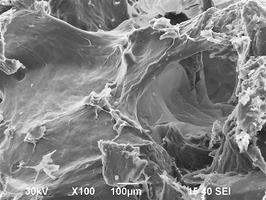

Биоимплантаты аллогенные стерильные губчатые механически и и ультразвуком обработанные.

2. Поверхность и структура материала для изготовления биоимплантатов